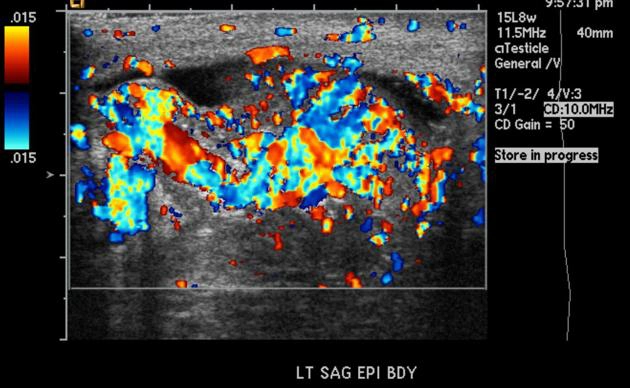

Viêm mào tinh (Epididymitis)